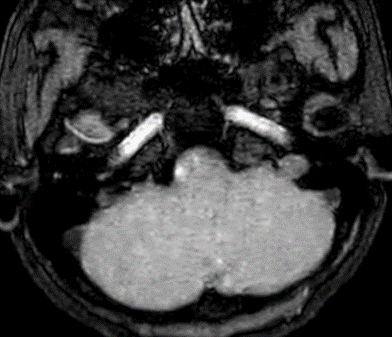

Các thăm dò hình ảnh khác như CT ngực, CT bụng và MRI sọ não không phát hiện tổn thương di căn.

Không phát hiện hình ảnh bất thường trên phim cộng hưởng từ sọ não